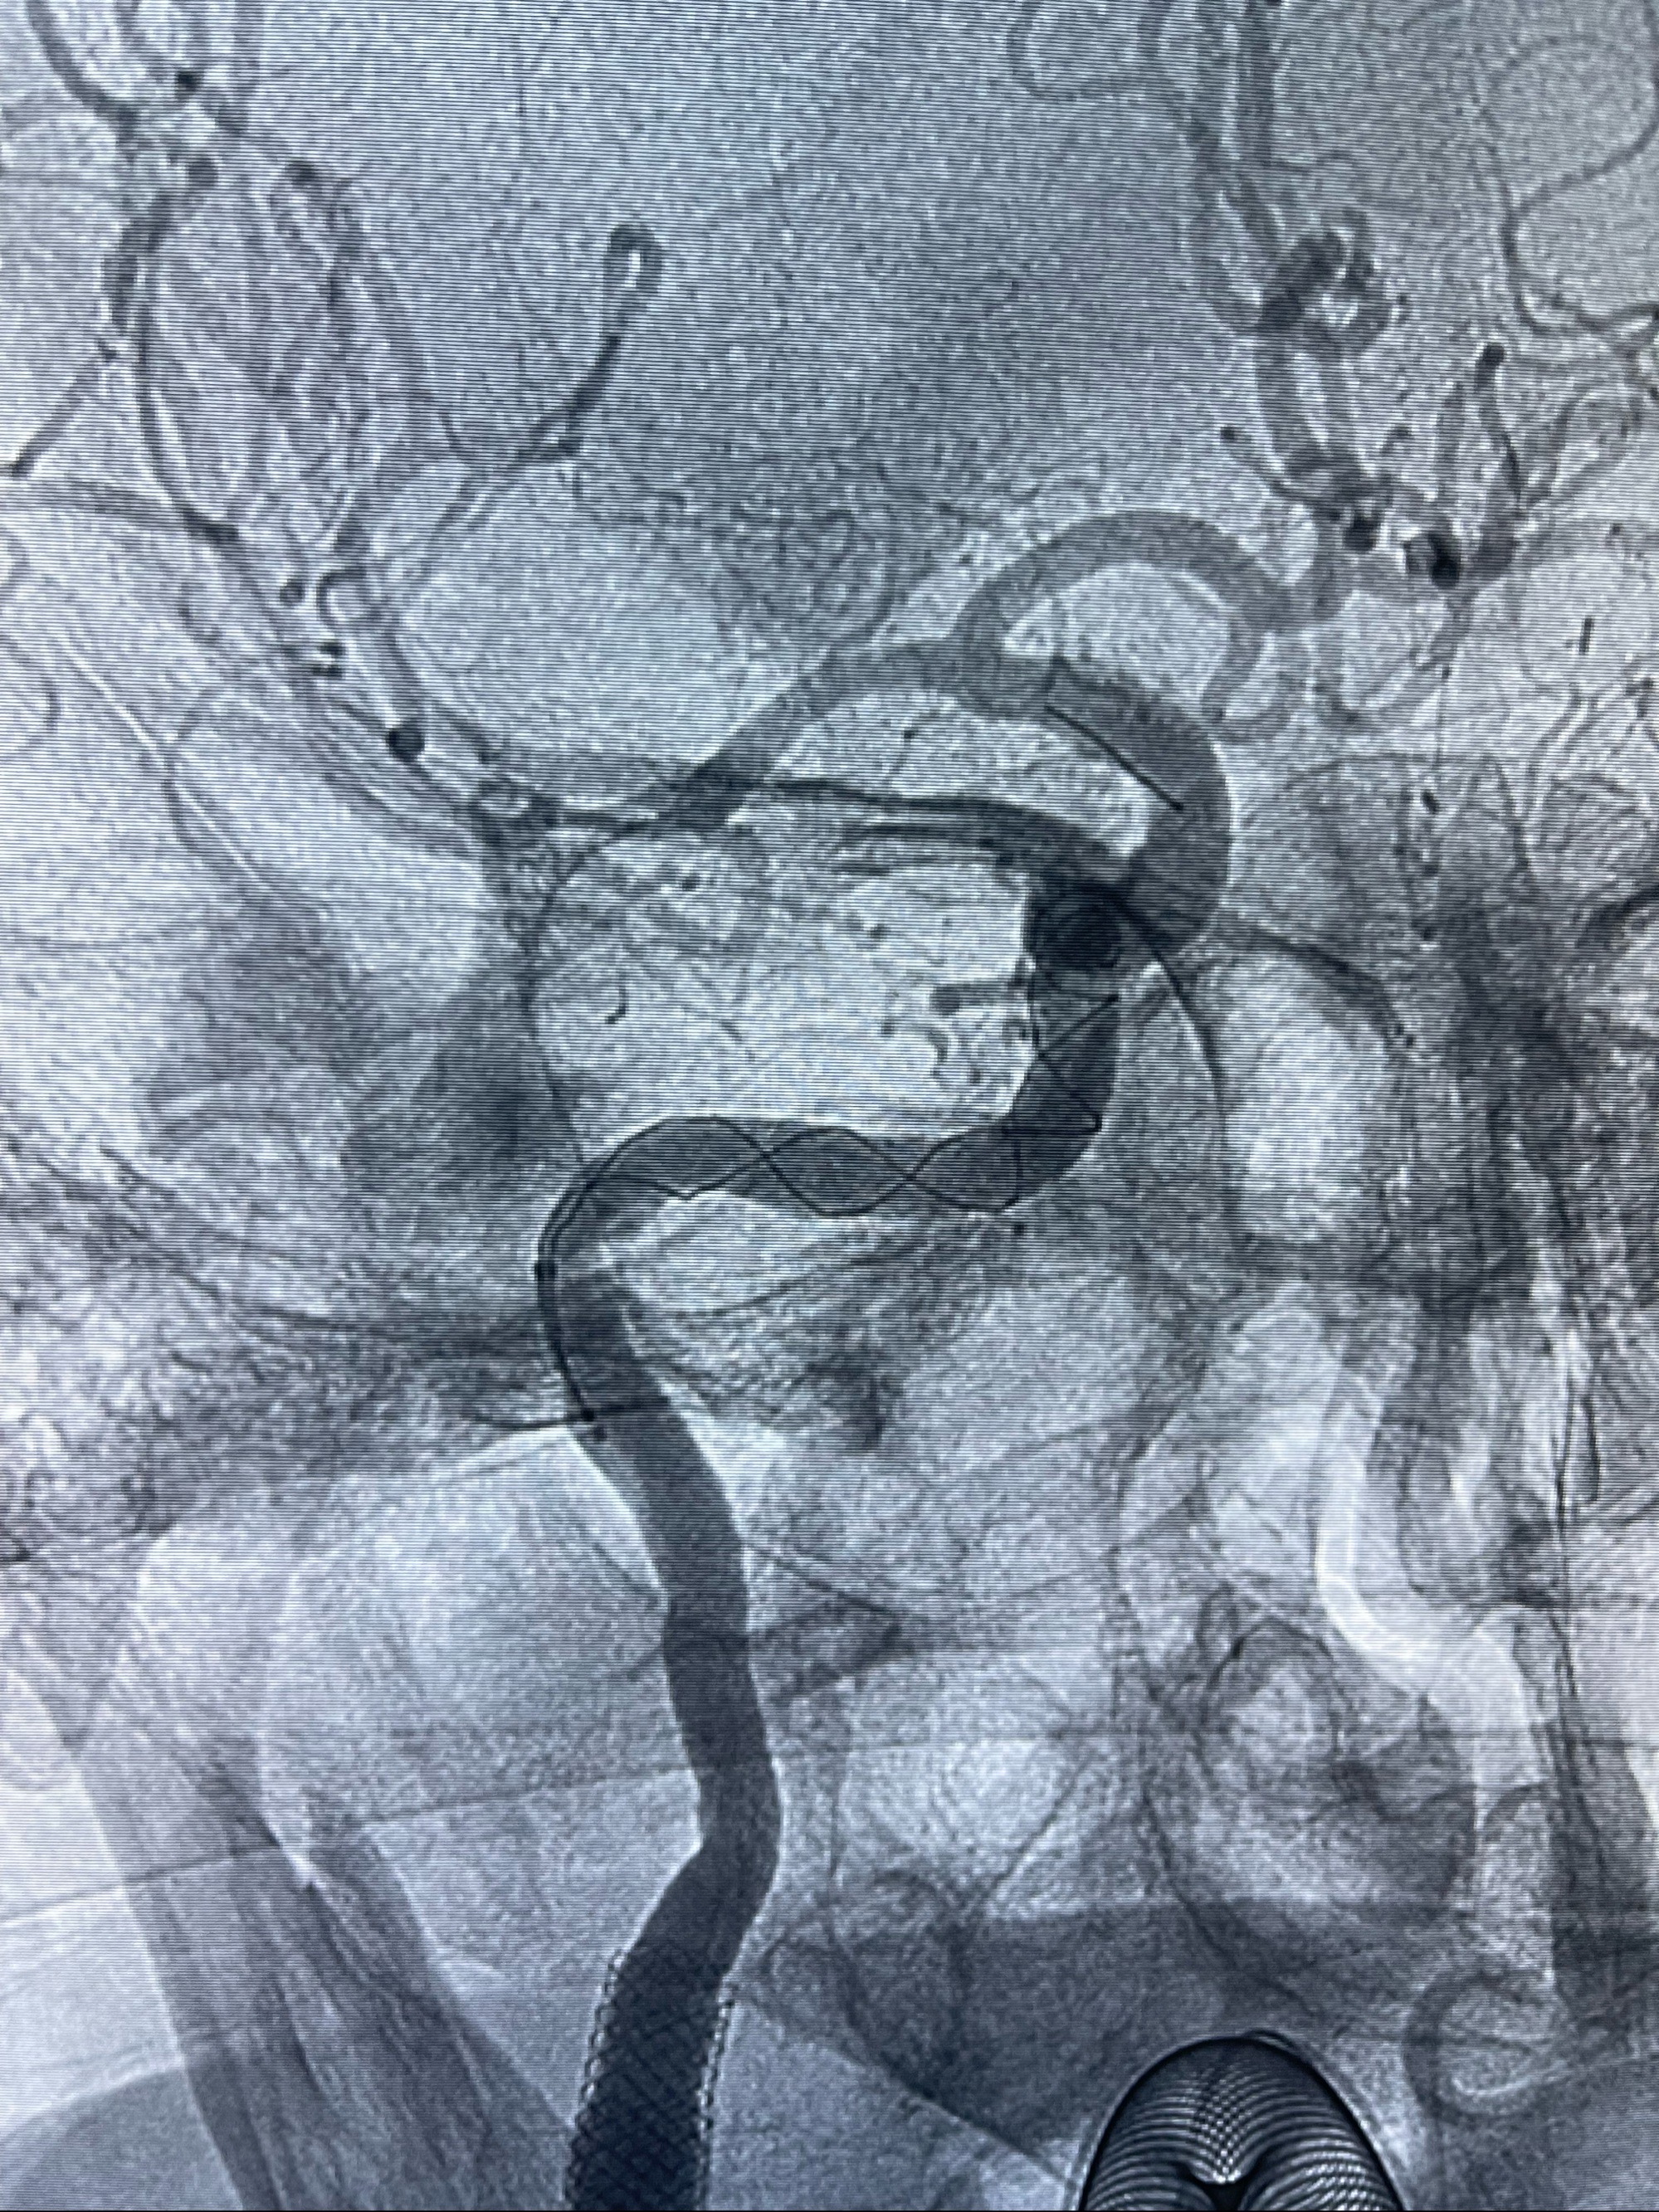

2023-07-10DSA:右侧颈内动脉岩骨段夹层伴中偏重度狭窄改变,左侧颈总动脉闭塞、右侧颈外动脉由右侧肋颈干甲颈干吻合代偿

箭头所示为颈内动脉岩骨段重度狭窄,结合MRI,考虑为肿瘤侵犯右侧颈内动脉

箭头以近至支架段管腔不规则狭窄

双抗准备后于2023-07-13在全麻下行右侧颈内动脉功能保护

088NeuroMAX100cm长鞘在125cmMPA及黑泥鳅导丝引导下超选择性插入右侧颈内动脉支架内

经导引导管造影显示支架远端颈内动脉不规则狭窄伴局部充盈缺损,同时行全身肝素化5ml

路径图下4-20mm球囊在导丝引导下超选择性至狭窄段,以6-8个大气压扩张,持续30s

泄除球囊造影显示局部管腔扩张佳

后移球囊至颈段狭窄段,以8-12个大气压扩张,持续30s后泄除球囊

即刻造影显示狭窄扩张佳

重新行“路径图”,支架导管在微导丝引导下超选择性插入至右侧颈内动脉眼段,4.5-50mmLeo支架释放,远心端位于海绵窦段,近心端位于岩骨段狭窄段以近

即刻造影显示支架贴壁佳

路径图下,5.5-50mmLeo支架导管在微导丝引导下超选择性插入远段Leo支架内

两枚支架部分重叠

多次确认支架位置及打开贴壁情况

支架完全打开,近心端位于原颈动脉支架远心端内